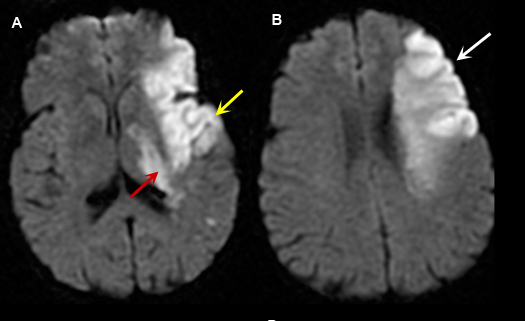

Figure 4: MR Images (DWI)

Left Middle Cerebral Artery Territory Acute Stroke

Imaging findings: Figure 4

- A and B: Diffusion weighted images shows areas of acute infarction as bright signal due to intracellular cytotoxic edema, restricting movement of water molecule in and out of the cell.

- In figure A, left temporal lobe acute infarction (yellow arrow) and left lateral basal ganglia-thalamic regions (red arrow) are noted.

- Left frontal lobe infarct (arrow) is shown in Fig. B.